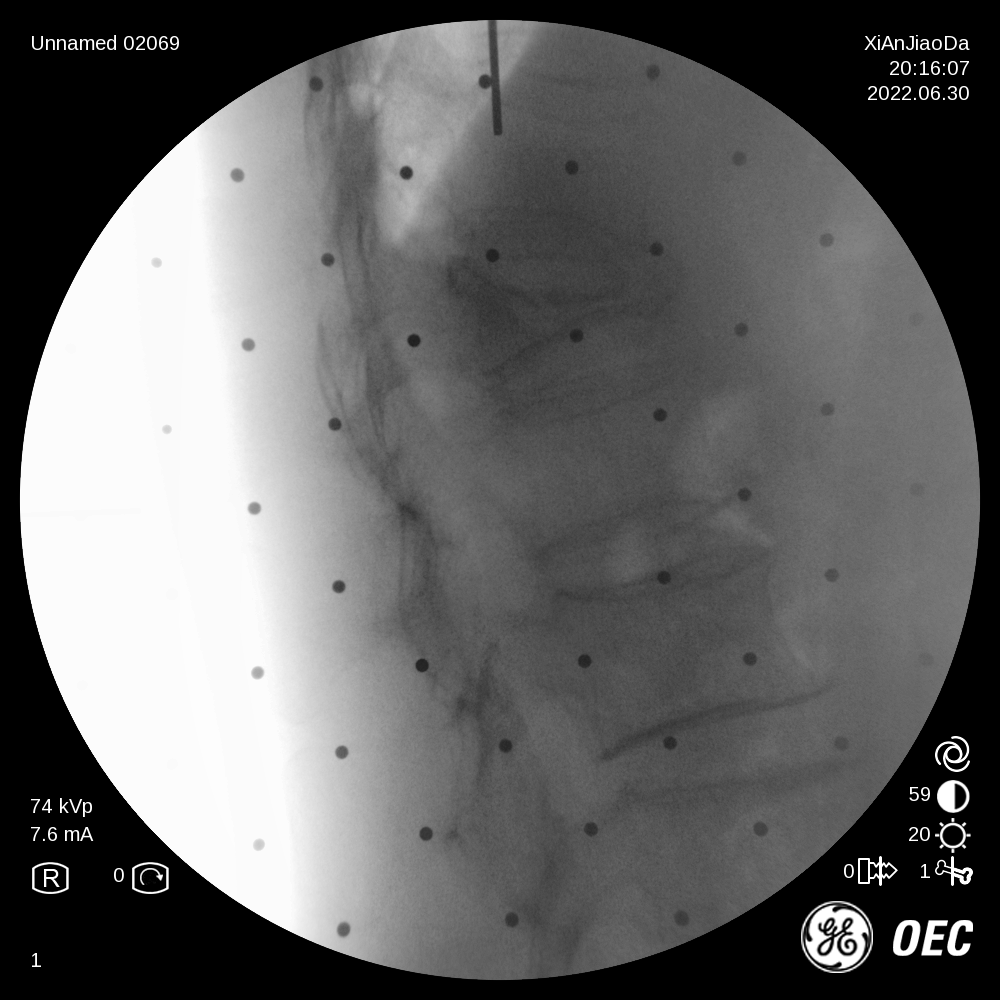

患者为一69岁女性,6月前摔倒后出现腰部疼痛伴活动受限,保守治疗后效果不佳遂来我院,经过诊断分析,该患者椎体重度压缩性骨折,重度骨质疏松致透视下骨性标志不明显,且存在轻微脊柱侧弯。王坤正主任团队最终决定运用智能化的手段,在局麻下行机器人辅助经皮椎体球囊扩张成形术,采取直观定位技术,相较其他机器人的定位导航技术,无需定位标志物,使得手术能够在全程局麻下操作,保证医生能得到患者的实时反馈,可使手术更精准、更便捷、更安全。

术前,王坤正主任团队采集患者的三维CT数据并将其导入到机器人术前规划系统中,机器人工程师与其配合确定穿刺位置、角度、深度等信息,制定出适合患者本人的个性化手术方案并在术中由机器人予以实施。

在该机器人辅助手术过程中,仅需通过正侧位进行伤椎识别,通过软件将正侧位透视图与术前规划数据的结合,即可得到病人伤椎的姿态以及实际的穿刺角度,之后机械臂根据软件参数进行精准定位,手术医生在机械臂引导下一次性进针成功,并对进针位置角度表示满意,整个过程少于20分钟,实现了手术的更精准化、高效化。相较于传统定位流程,术前规划只能保存在医生脑海中,术前与术中流程无法很好的衔接,术中穿刺依赖医生丰富的经验,对于情况复杂的病人,术中需要反复试验,导致手术时间延长、患者受辐射量增加。后续放置球囊、注入骨水泥等操作则同传统手工操作。